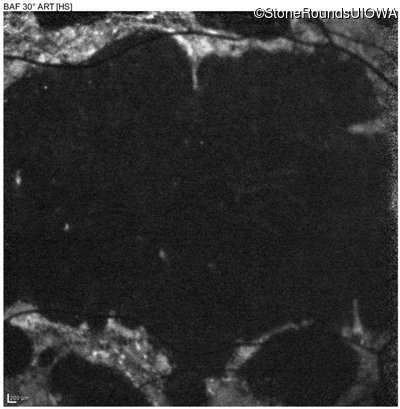

| AR Stargardt Disease | ABCA4 | Cys205Phe TGC>TTC | Gly863Ala (G)GA>(G)CA | AR |